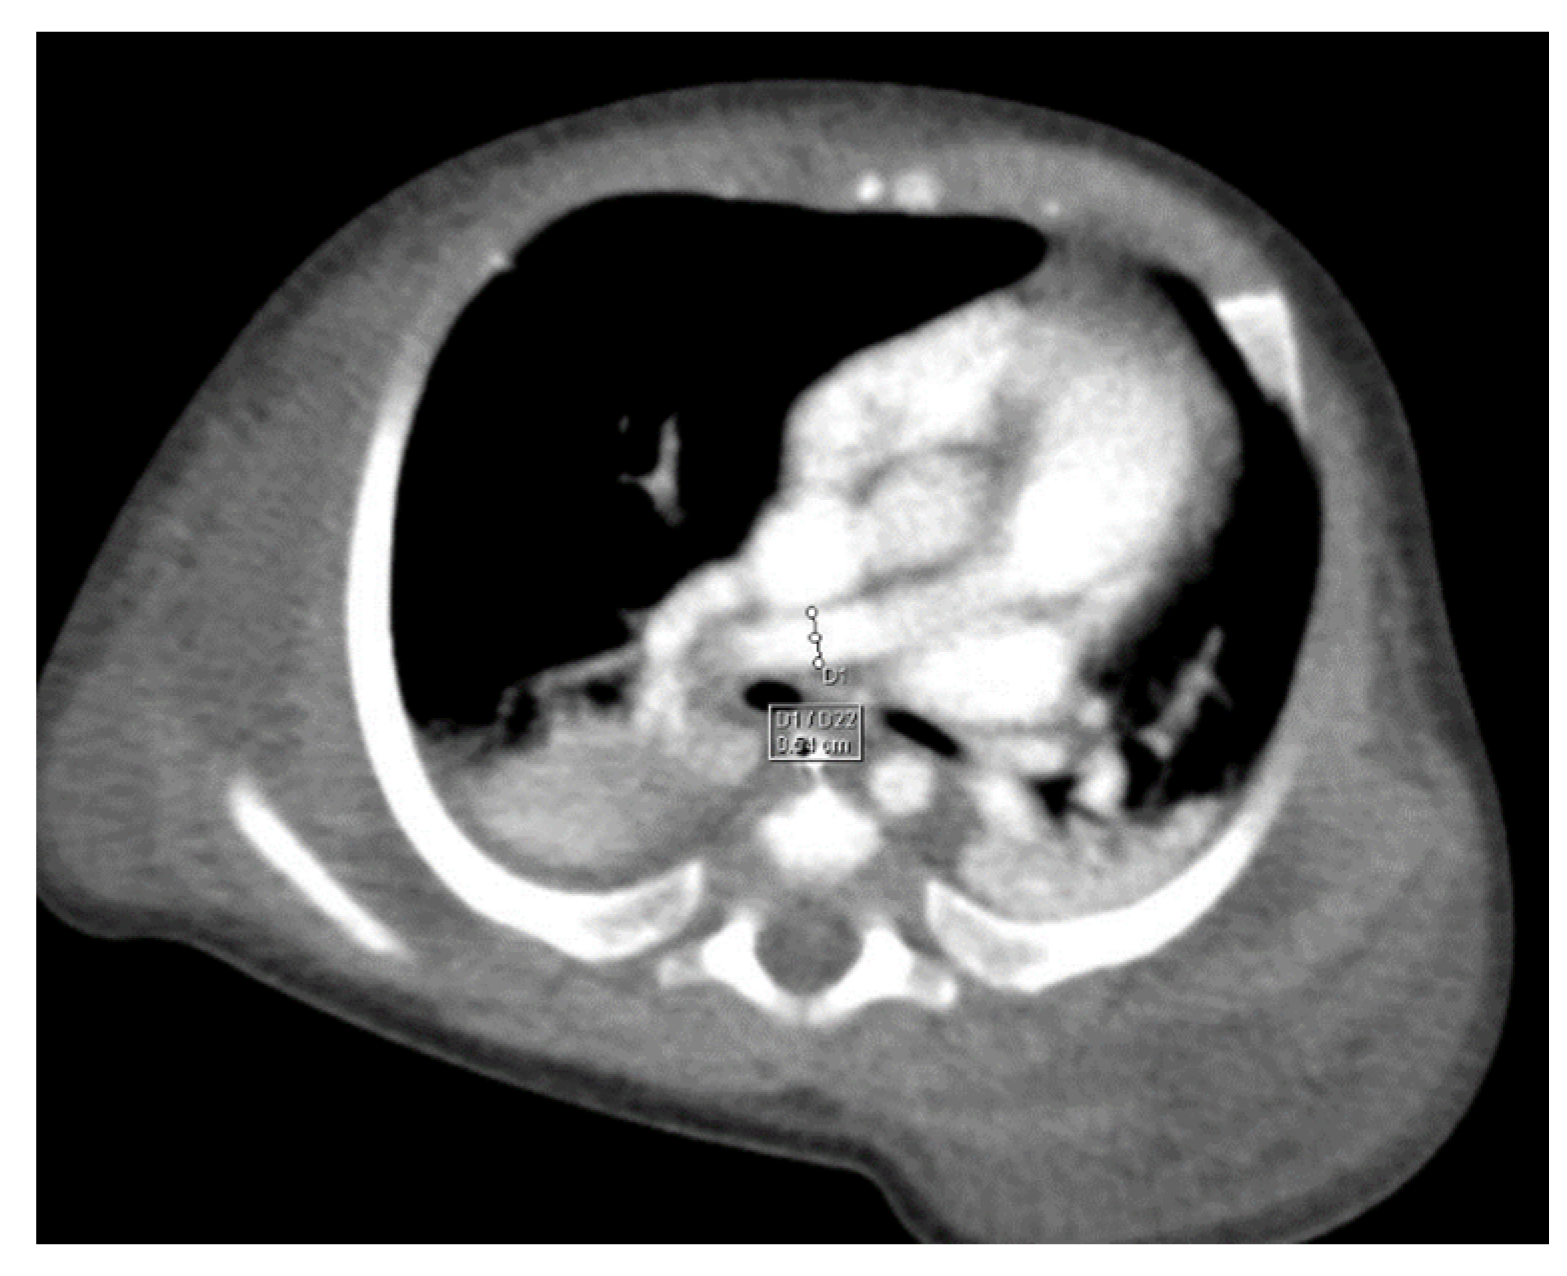

Through thoracic CT, we found SVC with a diameter of 15 mm (Figure 1), a venous collector with a 12 mm in diameter connected to the SVC and identified at the level of a plane passing through the middle of the left superior pulmonary lobe (Figure 2). The venous structure continues superiorly with the left brachiocephalic venous trunk, which was dilated up to 12 mm (Figure 3) and inferiorly with a left pulmonary vein. The pulmonary trunk appeared shorter, with a diameter of 6 mm, right pulmonary artery = 5.4 mm and left pulmonary artery = 5.6 mm (Figure 4 and Figure 5). We have identified traits of pulmonary consolidation (Figure 6).

Figure 2.

Venous collector.